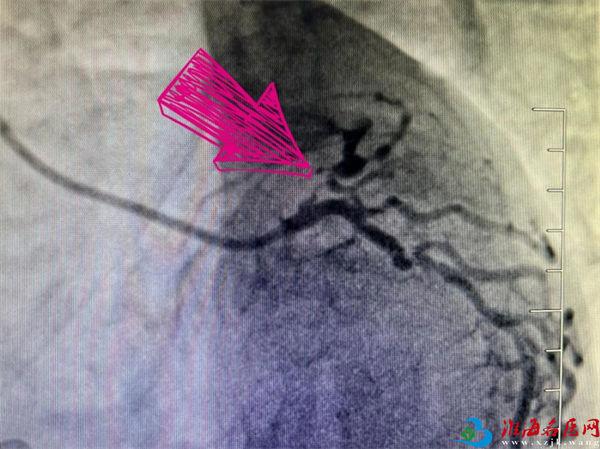

术前造影

导管室手术台上,黄先生的冠脉造影结果让所有人捏了一把冷汗:左主干开口狭窄50%,左前降支急性次全闭塞,中段慢性完全闭塞,其中开口-近段狭窄约95%-99%;右冠状动脉全程病变,中段慢性完全性闭塞!

“正常人心脏上冠状动脉主要有三根血管,分别是前降支、回旋支和右冠状动脉,其中任何一支血管堵塞都非常严重。患者两根血管堵塞,风险可想而知,随时会面临猝死的危险!”综合分析判断后,梁毅和团队决定先疏通罪犯血管——左前降支。